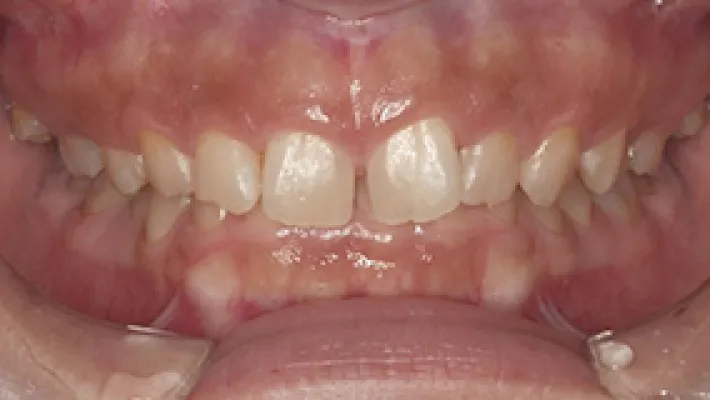

上下前歯すきっ歯 マウスピース矯正

施術前

施術後

マウスピース矯正の部分矯正で上下前歯のすきっ歯を改善した症例です。

状態にもよりますが、すきっ歯はマウスピース矯正の得意とするケースの一つです。

効率的な治療計画で最小限の期間と負担で矯正を行いました。

矯正治療の期間・方法

矯正治療の期間や方法は歯並びや顎骨などの状態によって大きく異なります。

矯正治療は歯や歯周組織などに必ずダメージがあります。

矯正治療のダメージを最小限にするために健康的で現実的な治療計画を提案します。

治療費

420,000

治療期間

4.5ヶ月